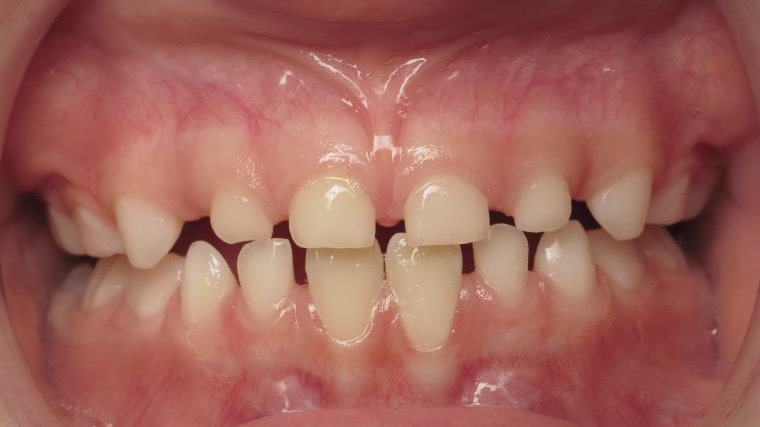

12 béance inversé droit 4 ans

inversion postérieur coté droit et espace entre les dents du haut et du bas (diastèmes)